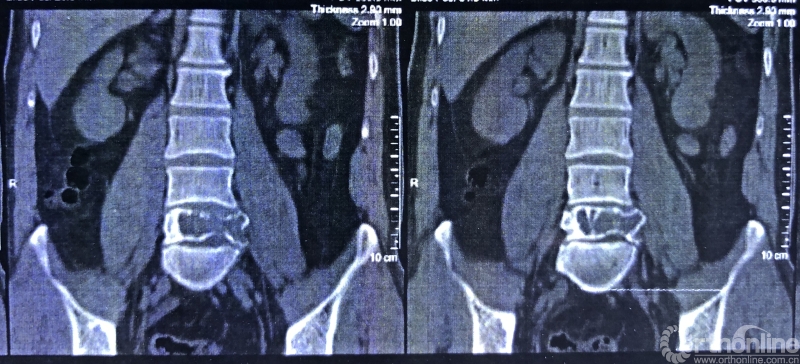

术前CT三维重建